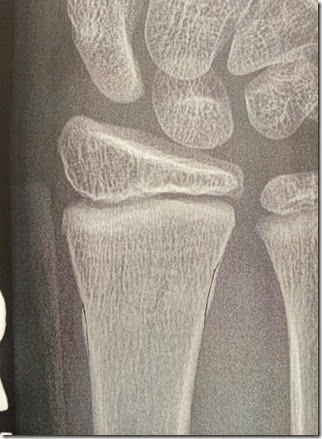

Notice where the radius bone (big arm bone to the left) bulges out slightly on both sides.

I drew lines to show where the true line of the bone should be.  That slight bulge or buckle was the proof apparently.

Verdict: Broken!  The technical term is “distal radius buckle fracture”.  Rock’s cousin helped us understand why we couldn’t tell it was broken by looking at this x-ray.  He said your bone is like a stick with a bunch of saran wrap around it.  If the stick breaks, the saran wrap holds it together if it’s not too big of a break.  And the “saran wrap” is pretty strong when you’re a kid.  That’s why it is so hard to see the actual break.